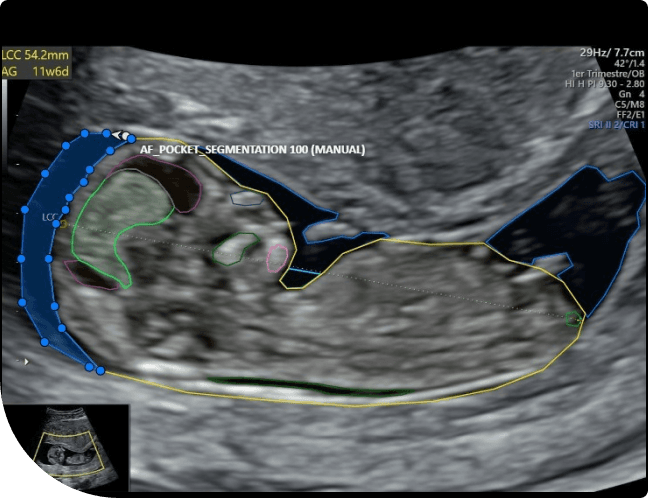

Logictive Solutions collaborated with Deepecho, a leading medical technology company, on a critical annotation project focusing on identifying and labeling various fetal anatomical structures in ultrasound images. The annotation work involved using polygon, polyline, and ellipse tools to precisely outline structures such as the Myometrium, Ventricles, Choroid Plexus, Cerebellum, Cisterna Magna, Humerus, Heart, Lungs, AF Pocket, Placenta, and Spine. The project aims to create an AI model to track all the above aspects related to Fetal helping in radiologist / specific medical section to smoothen their day to day processes and analyst.

Fetal Annotation based on Fetal Anatomy Ultrasound Annotation project was designed to support radiologists in identifying key fetal anatomical structures.

Using specialized annotation tools, our team annotated each ultrasound image, focusing on clarity, boundary accuracy, and structure differentiation.

Different CVAT annotation tools were applied depending on the anatomical structure’s shape to ensure maximum precision during the Fetal Annotation Execution phase.

Polygon Tool

Used for irregular structures like the placenta and lungs.

Ellipse Tool

Used for rounded organs like ventricles and cisterna magna.